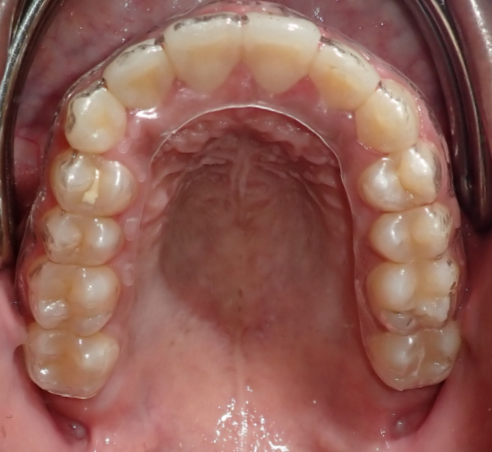

Close-up of the upper dental arch showing teeth and gums with a partial orthodontic retainer.

Retenedores y cuidado post-tratamiento

Una vez que se retiren tus brackets, te proporcionaremos retenedores personalizados y orientación para mantener tu sonrisa en su mejor estado durante muchos años.